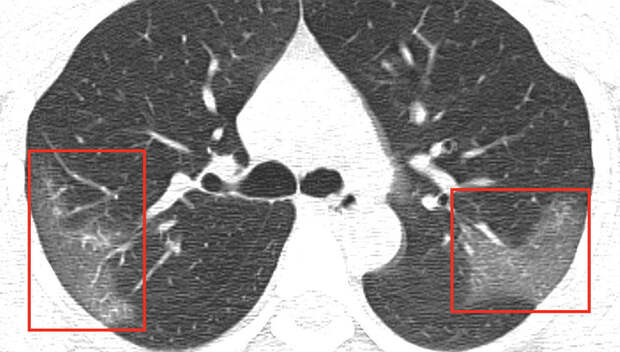

Опубликованы снимки компьютерной томографии легких, пораженных коронавирусом 2019-nCoV, сообщает издание Radiology. На сайте журнала, издаваемого Радиологическим сообществом Северной Америки (RSNA) уточняется, что снимки делали в Китае 33-летней пациентке, которая поступила в больницу с лихорадкой, высокой температурой и кашлем неизвестной этиологии.

Выяснилось, что больная работала в эпицентре вспышки нового коронавируса 2019-nСоV – в Ухане, но за неделю до госпитализации приехала в Ланьчжоу.На первом снимке видны помутнения, создающие «эффект матового стекла». На повторном снимке, который был сделан после трех дней лечения, можно заметить, что заболевание прогрессирует, область помутнения увеличилась. О состоянии пациентки и жива ли она не сообщается.